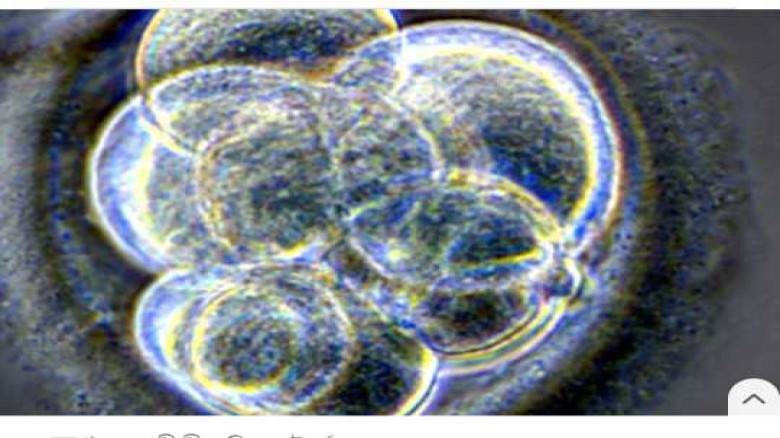

৩০ বছরের পুরোনো হিমায়িত ভ্রূণ থেকে শিশুর জন্ম।...